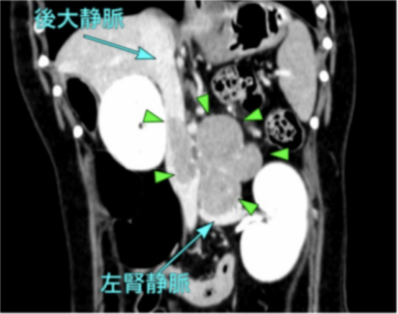

肝臓腫瘤